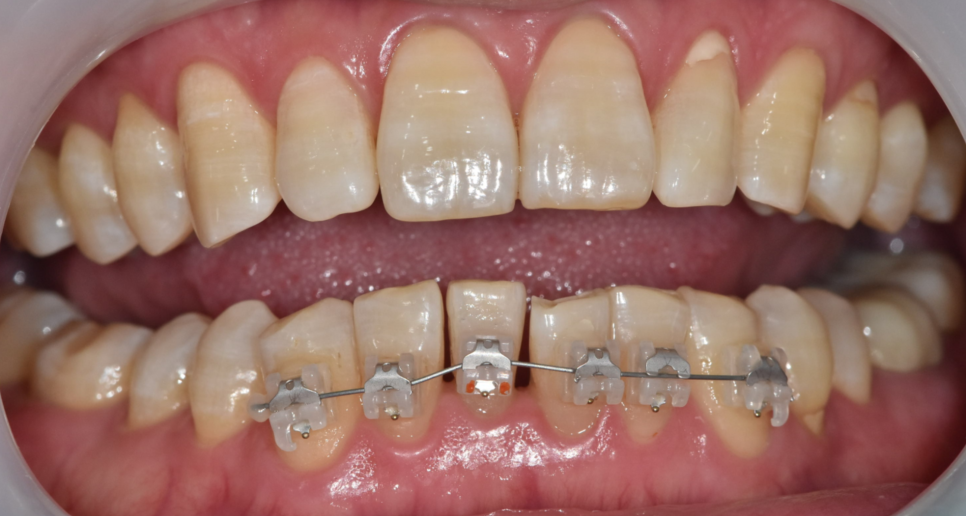

250425 부분 교정도 고려해볼 수 있습니다 .

50-60대분들도

성인 교정 충분히 가능합니다 .